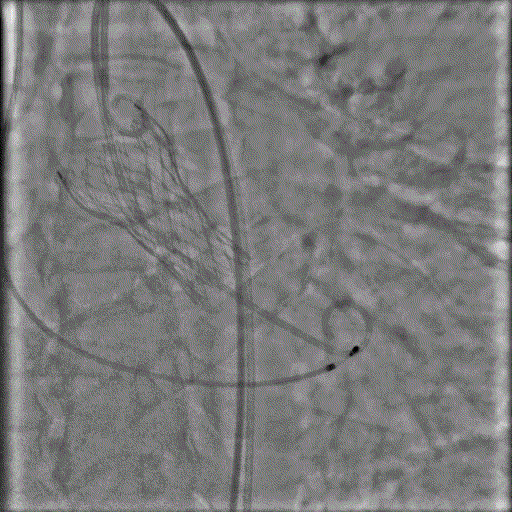

陈伯年纪较大,术前心脏超声显示主动脉瓣重度狭窄,跨瓣峰值压差达86mmHg,估测主动脉瓣口面积只有 0.66c㎡,随时有猝死危险。老人家合并多种临床疾病,自身对开刀手术十分惧怕,了解到何鹏程教授带领的心血管内科介入团队水平好评价高,因此从茂名慕名远道而来接受进一步治疗。患者入院后,何鹏程教授组织心血管内科、麻醉科、超声医学科、胸心外科和乳腺外科等多学科进行了详尽的术前讨论,制订了精细的手术方案,仅仅通过从大腿血管处置入的导管就顺利完成瓣膜输送、定位和释放的全过程,心瓣膜释放后原来高达86mmHg的压力阶差完全消失,意味着原来存在的严重瓣膜梗阻完全消除,心脏彩超也显示主动脉瓣人工瓣膜功能良好,手术获得圆满成功,陈伯在手术第二天即可下床行走,术后一星期即康复出院。

▲何鹏程教授团队术中

▲植入后的瓣膜形态良好、功能佳

▲术后压差为0,效果非常理想